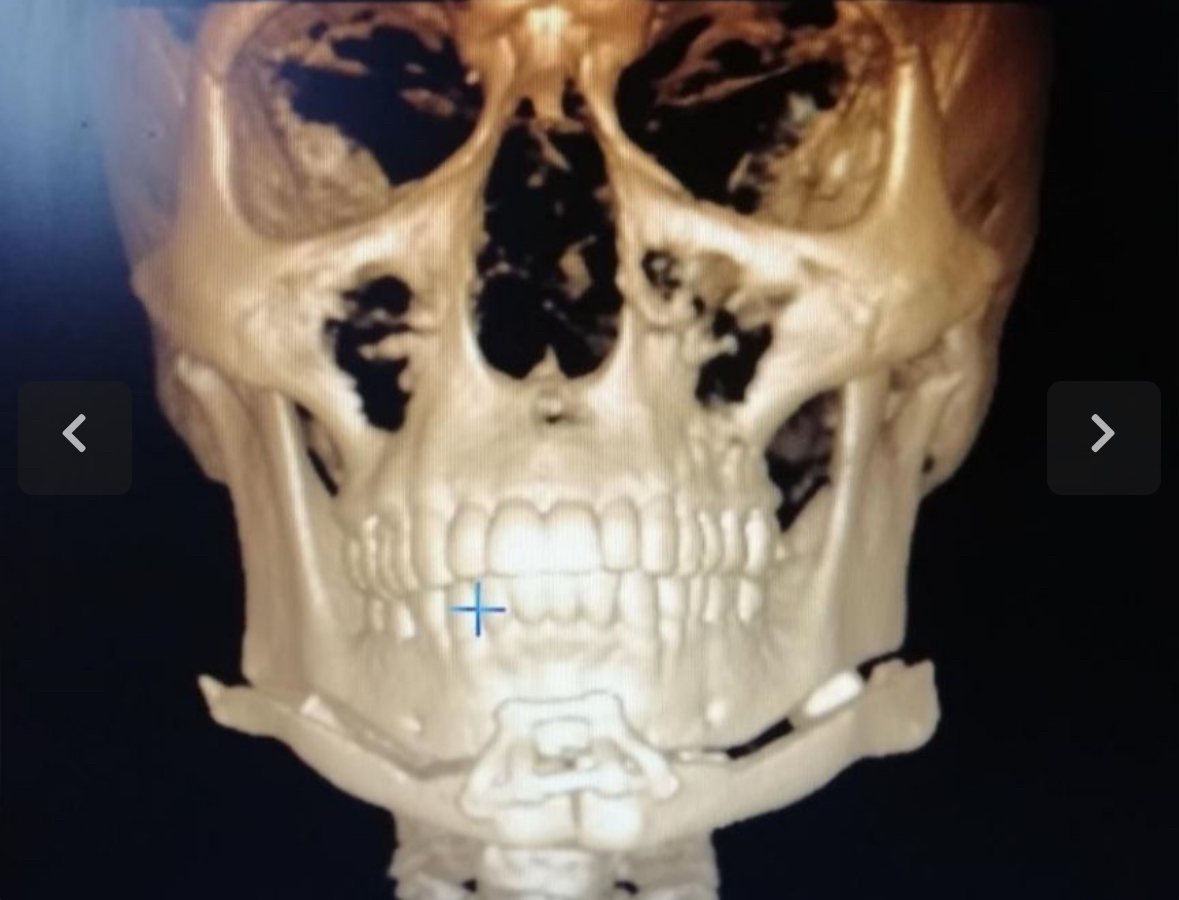

I want to fix my gonial angle and the only way to do that is by lengthening my ramus . What are the options here ?

Vertical jaw angle implants.Obviously I am talking about hardmaxxing i am 16 rn

why not high G filler?The default answer would be jaw angle implants, but i wonder if the osteotomy bossman suggested is approved by the people here

It's just a segmented chin wing, isn't it ? If so, I don't know why @bossman didn't call it by its name. A regular chin wing can lengthen the ramus and modify the gonial angle. Search "chin wing", and you'll find enough documentation.the osteotomy bossman suggested

I feel as if this isn't a good way to address lowering the ramus/decreasing the gonial angleThe default answer would be jaw angle implants, but i wonder if the osteotomy bossman suggested is approved by the people here

For alot of people who are downgrown that seek this treatment the wing cut would need to be spaced out alot in order to achieve the ideal and with that comes instability - in theory it reminds me of a maxillary downgraft which requires autologous bone grafts/Hydroxyapatite blocks and rigid plates to affix it. Even then there are many studies that show relapse/non union - this technique is done by very skilled surgeons to have successful union and results. It's just too invasive and causes problems and since most surgeons aren't doing it or practising it I doubt it would be possible

I think it could be used to slightly increase the ramus length and lower the gonial angle (but to what visible effect? Is it even worth it at that point to go through an invasive osteotomy just for that?) but won't be able to replace jaw angle implants. I have never seen a chin wing be able to produce posterior height it's mainly used front profile jaw width

Thats probably the easiest permanent result hardmaxx for ramus tbh but I am not sure if the surgery is easy to get messed up or if its really dangerousVertical jaw angle implants.

So you think implants is the way to go?I feel as if this isn't a good way to address lowering the ramus/decreasing the gonial angle

For alot of people who are downgrown that seek this treatment the wing cut would need to be spaced out alot in order to achieve the ideal and with that comes instability - in theory it reminds me of a maxillary downgraft which requires autologous bone grafts/Hydroxyapatite blocks and rigid plates to affix it. Even then there are many studies that show relapse/non union - this technique is done by very skilled surgeons to have successful union and results. It's just too invasive and causes problems and since most surgeons aren't doing it or practising it I doubt it would be possible

I think it could be used to slightly increase the ramus length and lower the gonial angle (but to what visible effect? Is it even worth it at that point to go through an invasive osteotomy just for that?) but won't be able to replace jaw angle implants. I have never seen a chin wing be able to produce posterior height it's mainly used front profile jaw width